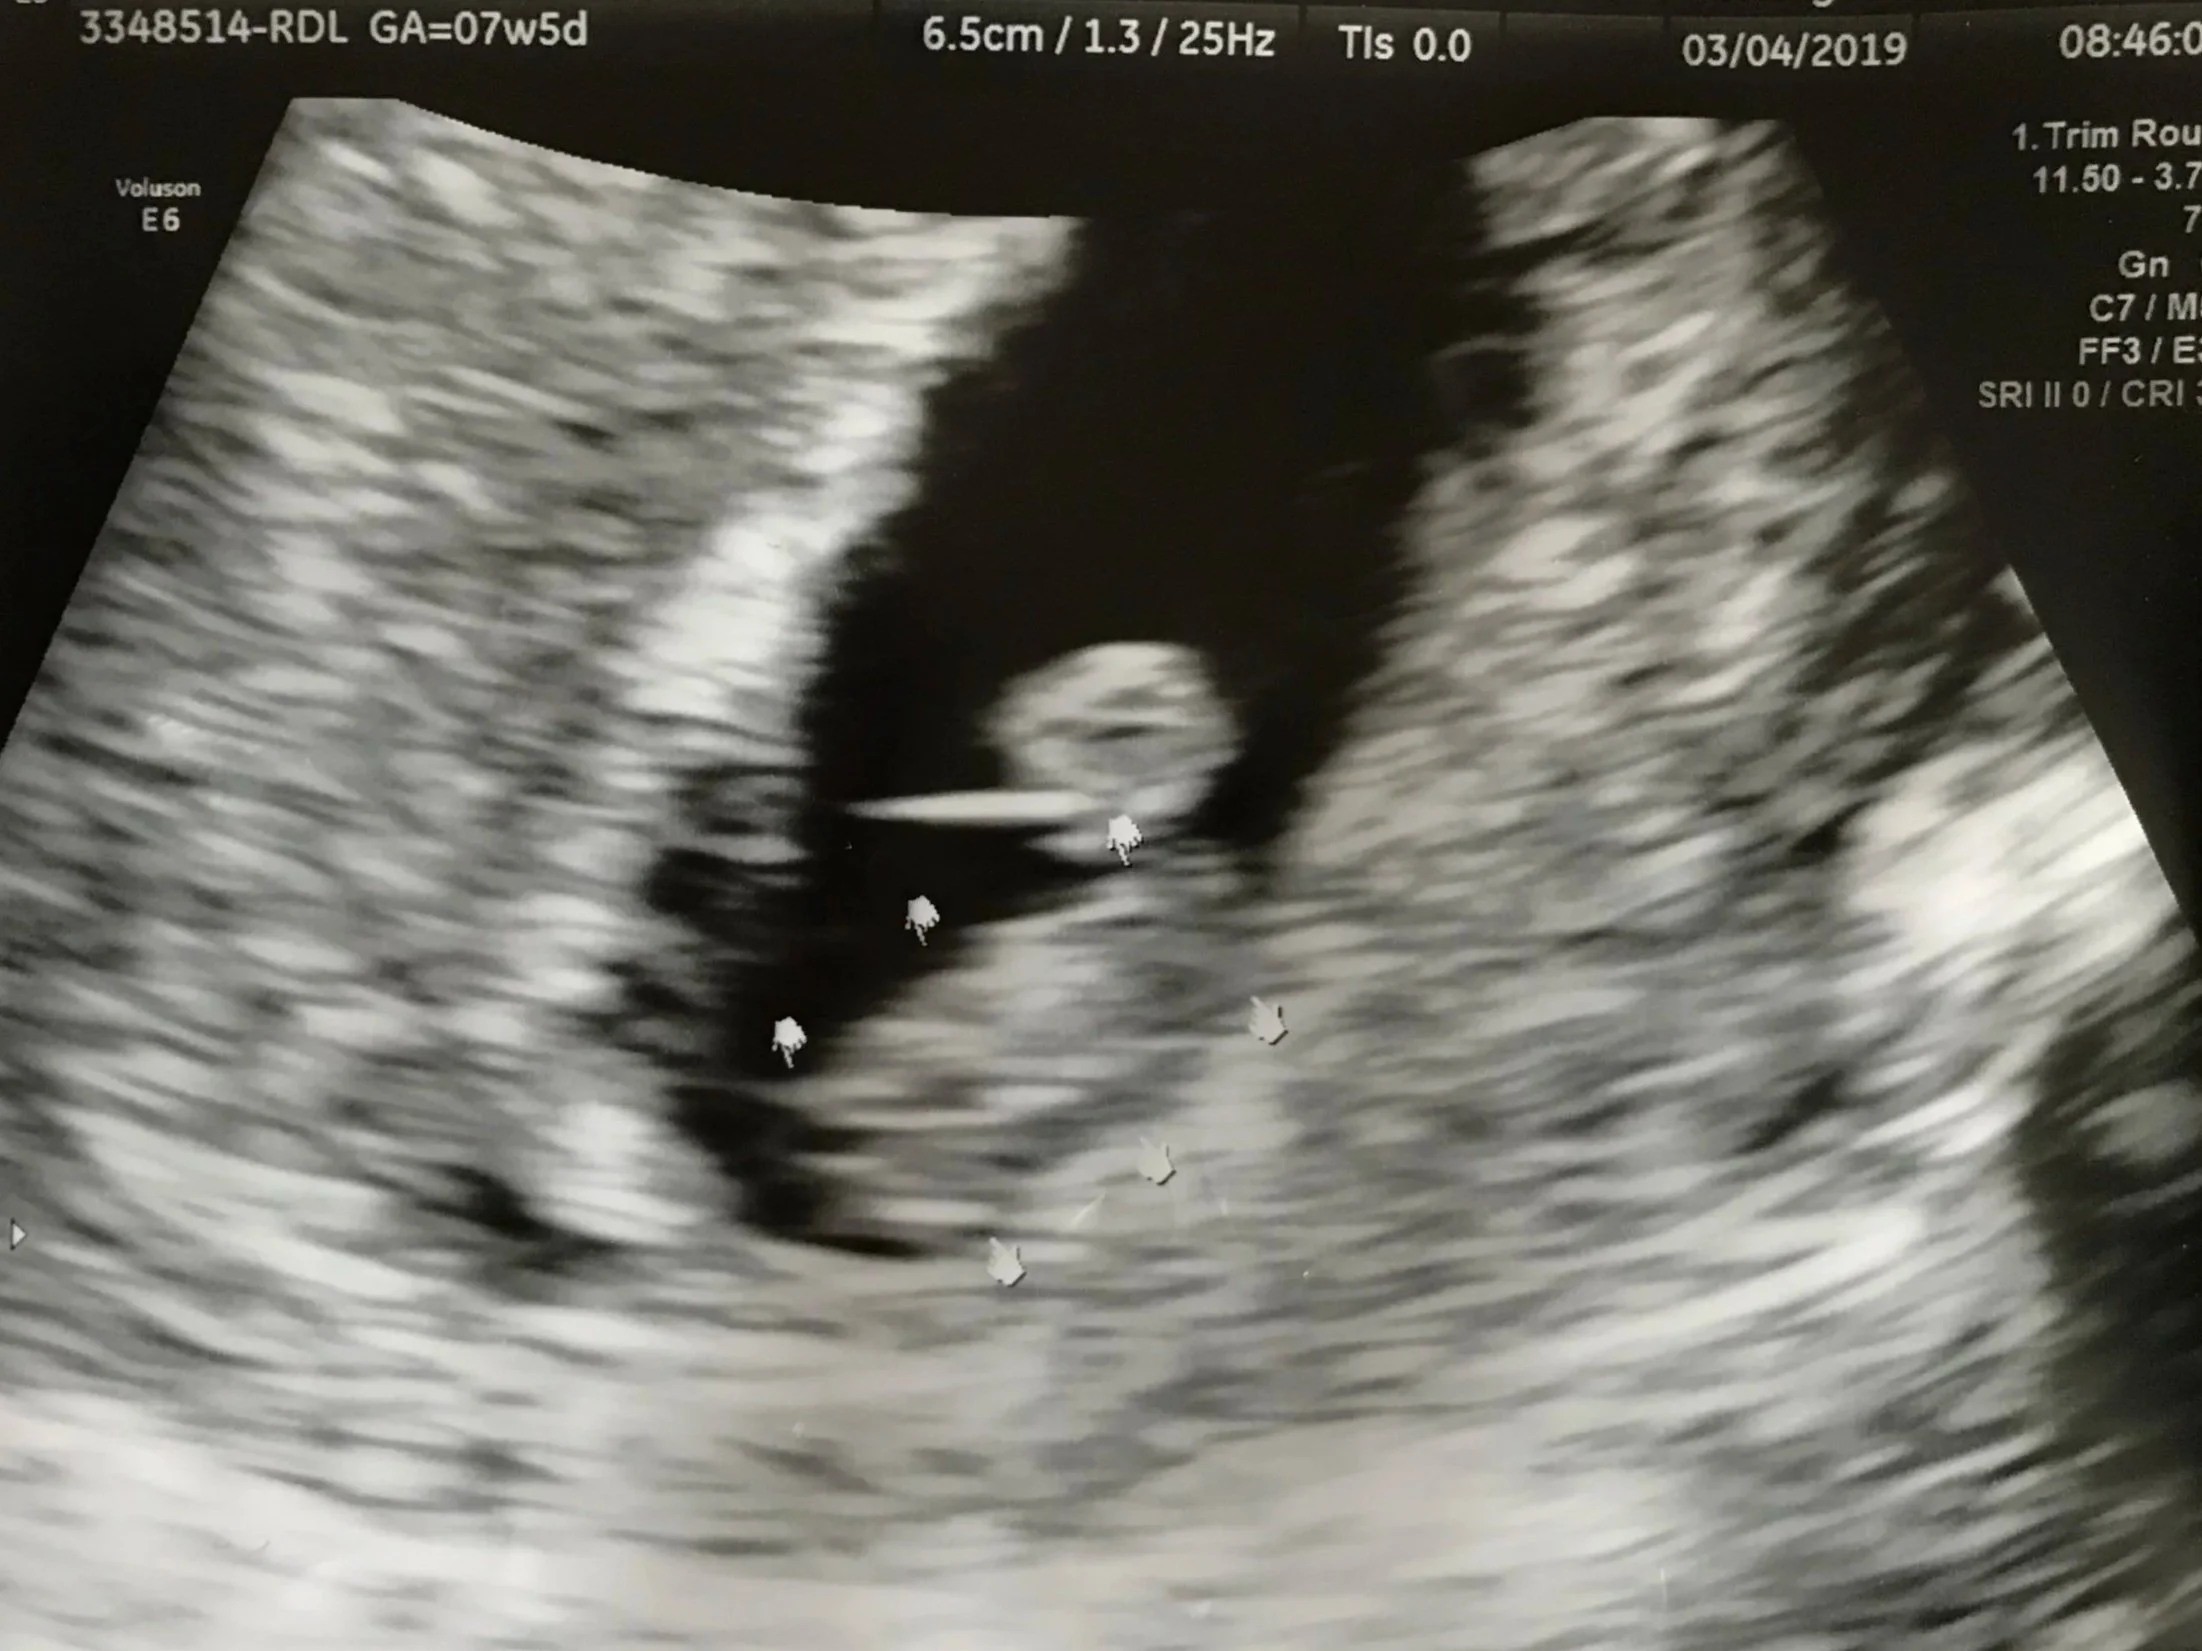

As I continued to work through the sadness that my babies had passed, I learned to cherish the moments I saw their hearts beat, their blurry pictures, felt my belly growing, and the initial excitement of possibly being a mom. No matter what the world’s opinion was, it is okay for me to love them so deeply and cherish every second I carried them here on earth. It is also okay for me to feel broken because I could not give them a life here on earth, what was not okay was for me to walk that path of heartbreak alone.